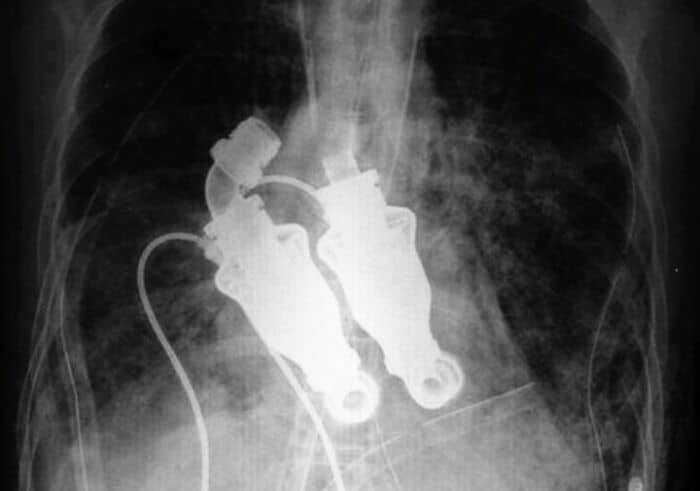

#60 Doctors From The Texas Heart Institute Have Performed A Surgery Implementing A Device That Left A Man Becoming The World’s First Heartless Human Leaving Him Without A Pulse Or Detectable Heart Beat

#61 $8,500 Worth Of Medical Equipment In The Us. My Son Needs These To Walk